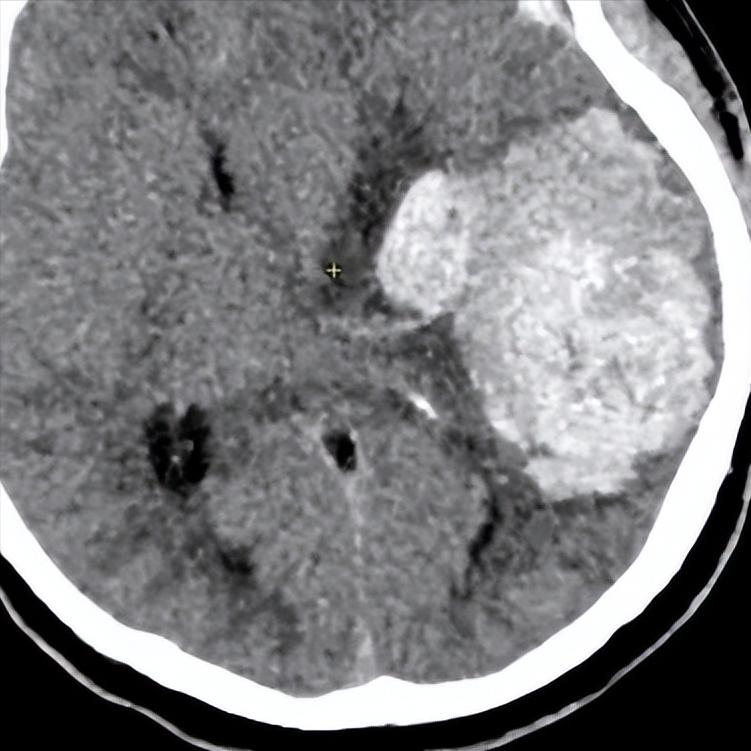

是肿物还是椎间盘?如果不出意外的话,应该是一块超大的椎间盘脱出